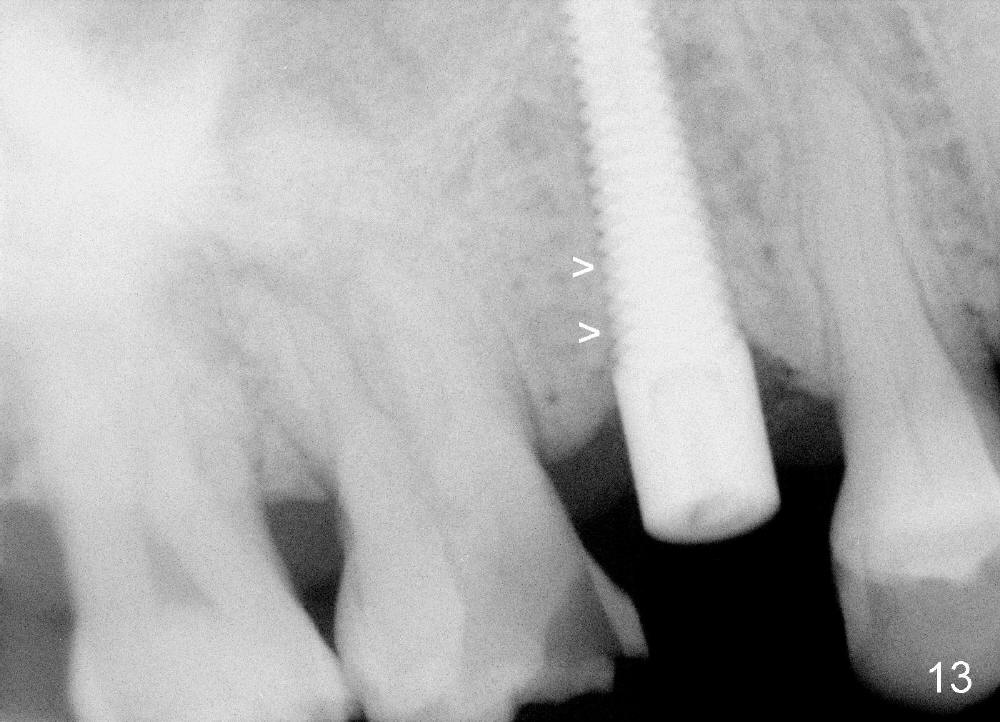

Five and a half months postop, the distal gap appears to have reduced (Fig.13 >).  Clinically the implant is stable and is ready for restoration.  It is advisor able to watch those asymptomatic immediate implants with minimal mobility.  It takes time to osteointegrate the immediate implant considering the peri-implant space.